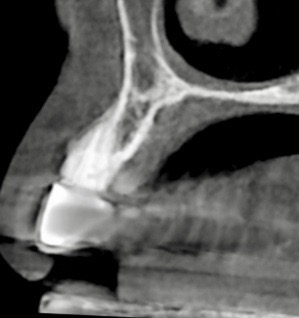

下記の症例は骨幅が薄く、このままでは長期的に安定したインプラント治療が不可能だったので、抜歯と同時に骨造成(GBR)を行い、その後歯肉移植(FGG)を行い、術後安定した経過を辿るよう配慮致しました。